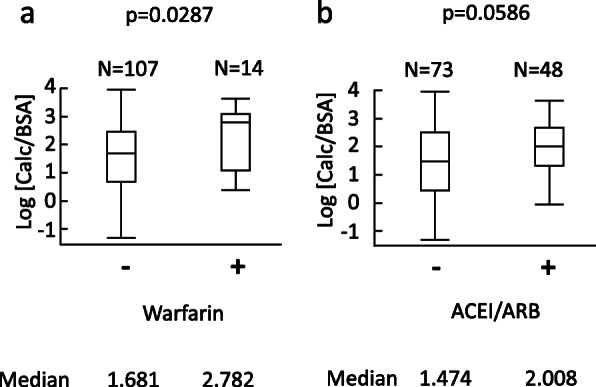

Fig. 3.

The relationship between warfarin or ACEI/ARB and vascular calcification volume. In univariate analyses, use of warfarin was significantly associated with vascular calcification volume (p = 0.0287). ACEI/ARB was marginally associated with vascular calcification volume (p = 0.0586). a, warfarin. b, ACEI/ARB. ACEI, angiotensin-converting-enzyme inhibitor; ARB, angiotensin II receptor blocker; BSA, body surface area calculated with Fujimoto’s formula; Calc, calcification volume

The characteristics of the 121 patients (mean age, 71 ± 12 years; 72 men) included in the analysis are provided in Table 1A. Among these patients, the median Calc was 8.94 (3.26 - 18.9) mL, and the median Calc/BSA was 5.62 (2.01 - 12.7) mL/m2. The mean log [Calc/BSA] was 1.67 ± 1.20. The mean log [eGFR] was 3.1 ± 0.8, which corresponds to an eGFR of 20.2 (11.8 - 40.3) mL/min/1.73m2. The relationships between log [Calc/BSA] and either of age, log [eGFR], SBP, warfarin, diuretics, malignancy or ACEI/ARB were investigated. Log [Calc/BSA] was significantly associated with age (p < 0.0001), log [eGFR] (p = 0.0226) or systolic blood pressure (p = 0.0306) as shown in Fig. 2. The association of warfarin with log [Calc/BSA] was significant (p = 0.0287). The association of ACEI/ARB with log [Calc/BSA] was marginally significant (p = 0.0586) (Fig. 3) Moreover, the association of diuretics with log [Calc/BSA] was significant (p = 0.0020). The association of malignancy with log [Calc/BSA] was not significant (p = 0.8414). In univariate analyses, the difference of the median values of log [Calc/BSA] was 1.10 with or without warfarin (Fig. 3). That was 0.53 with or without ACEI/ARB (Fig. 3).